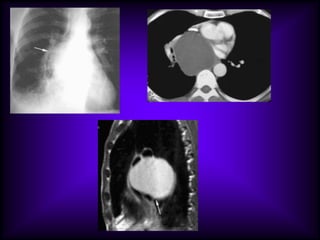

The CT features of benign

mediastinal cyst are

(a) a smooth, oval or tubular mass with a well-

defined thin wall that usually enhances after

intravascular administration of contrast

material,

(b) homogeneous attenuation, usually in the

range of water attenuation (0–20 HU),

(c) no enhancement of cyst contents, and

(d) no infiltration of adjacent mediastinal

structures.

Cysts that contain serous fluid typically have

long T1 and T2 relaxation values, which

produce low signal intensity on T1-weighted

MR images and high signal intensity on T2-

weighted images.

Because cysts containing nonserous

fluid can have high attenuation at CT,

they may be mistaken for solid

lesions. MR imaging can be useful in

showing the cystic nature of these

masses because these cysts continue

to have characteristically high signal

intensity when imaged with T2-

weighted sequences regardless of the

nature of the cyst contents